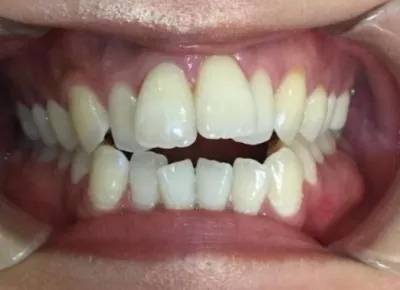

Before

After

治療期間

費用総額